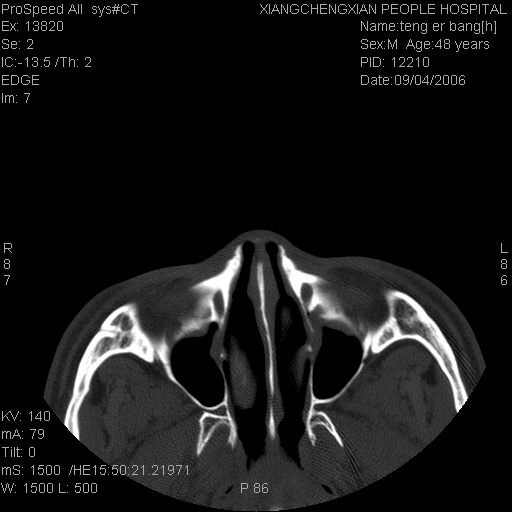

患者,男,以头面部外伤后头疼1小时为主诉入院,患者1小时前被他人打伤头部及左侧面部,眼睑无水肿,左侧面部肿胀压疼,未触及骨擦音。专科检查:耳鼻喉未见异常。

ct:平扫+冠扫:双侧鼻骨对比,冠扫s6#示右侧鼻骨尖部可见线状低密度影,边缘光滑,并见硬化.软组织未见肿胀.

诊断意见:鼻额缝(鼻骨与上颌骨额突缝),但个别同志认为是骨折.因此请同行们会诊.多谢了!

正常鼻颌缝。软组织无肿胀。鼻腔无积液积血。鼻骨光滑规整无中断。均不支持骨折。

正常的,双侧对称.边缘光整,且逢等宽.

正常鼻颌缝。软组织无肿胀。鼻腔无积液积血。鼻骨光滑规整双侧对称。均不支持骨折。